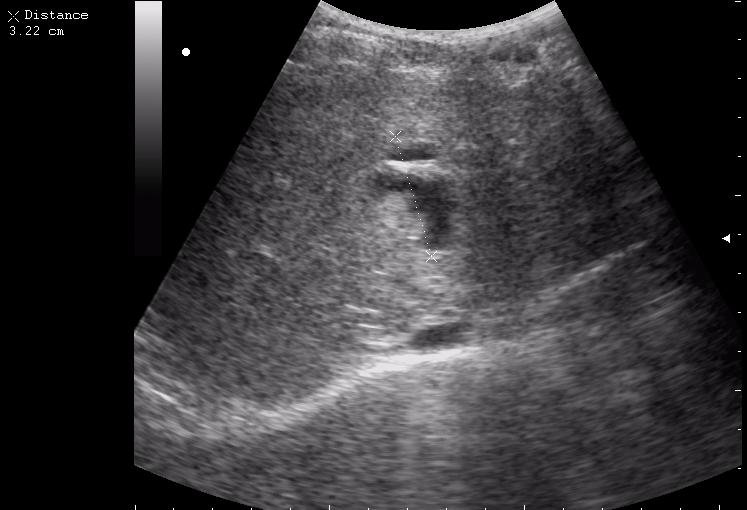

12-перстная, несмотря на свой пугающий вид, целая